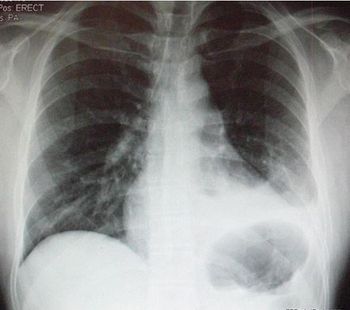

Recovery from a hemopneumothorax had progressed well for this 29-year-old man until today when he presents to the ED with dyspnea and pleuritic chest pain. What do you see on the chest x-ray?

Persistent symptoms of hemothorax or pneumothorax, in the absence of new x-ray findings require further inquiry, including chest CT, to rule out PE.